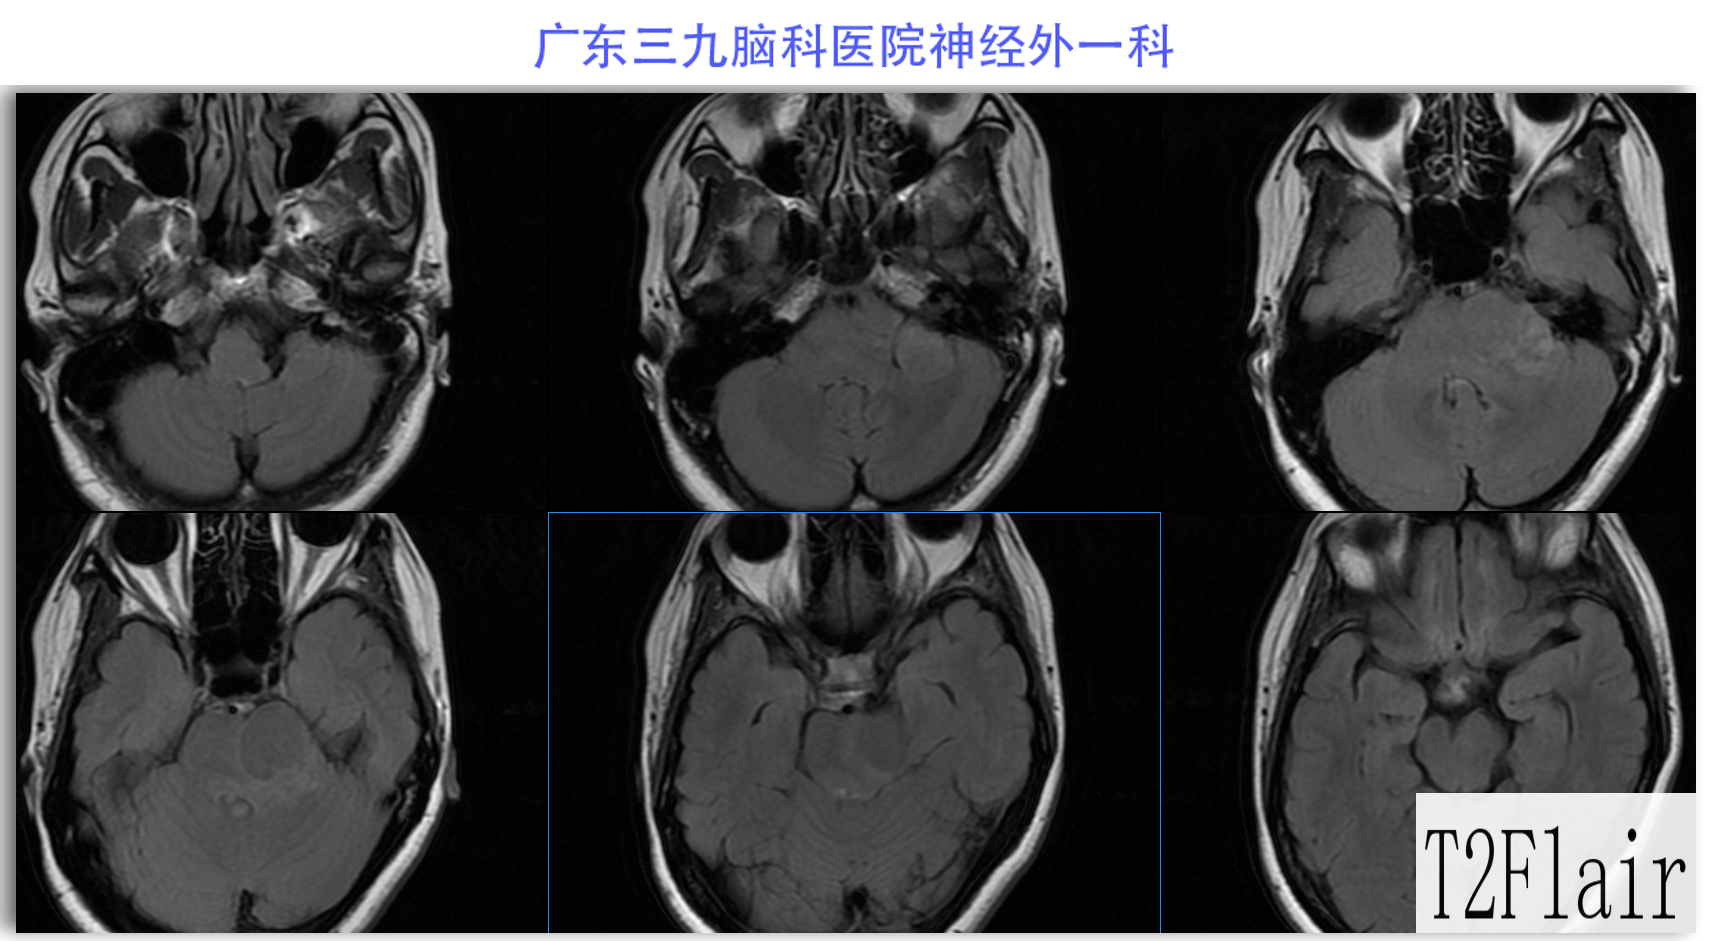

陈某某,女,41岁,因“左侧面部麻木3月余,吞咽困难半月余”于2024-02-17入院。患者3个月前出现左侧面部麻木,偶尔伴有头晕和左侧流泪,但没有听力下降或耳鸣。同时,患者也出现肢体乏力和行走不稳,但未接受任何治疗。半个月前,患者发现吞咽硬质食物稍有困难,同时左侧面部麻木加重。因此,前往当地医院就诊,并进行头颅MR检查,结果显示左侧CPA区存在占位性病变。为了进一步治疗,患者转诊至我院就医。术前检查显示:左侧角膜反射减弱,左侧鼻唇沟略微变浅,伸舌稍微右偏,咽反射迟钝。门诊诊断为“左侧巨大听神经瘤”,收治至我科进行住院治疗。手术过程顺利,术后患者恢复良好,面部轻度瘫痪与术前相同。术后病理检查结果确认为听神经瘤。